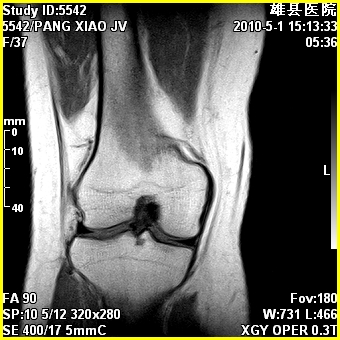

标题: MRI2894:患者右膝关节疼痛两月余,无明显外伤史 [打印本页]

标题: MRI2894:患者右膝关节疼痛两月余,无明显外伤史

右股骨下端前内侧类圆形异常信号,位于干骺端,呈长t1长t2改变,但信号不均,t1图上病灶中心见小片状稍高信号影,t2图上见散在稍低信号影,stir像呈高信号,因病灶较小,缺乏特征性改变,结合患者年龄及部位,考虑嗜酸性肉芽肿可能性大。胫骨关节面下的小囊状异常信号,如果一元论考虑则为嗜酸性肉芽肿,不过发生在这个部位的少见,二元论考虑为邻关节骨囊肿。半月板与前后交叉韧带均未见异常。

临关节骨囊肿可优先考虑